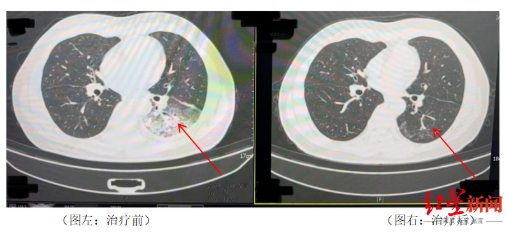

李先生肺部治療前與治療后的對比

起初,他以為是吹空調(diào)吹感冒了,于是自行服用感冒藥,但病情并未好轉(zhuǎn),反而愈發(fā)嚴(yán)重。家人見狀,立即將他送往成都市第五人民醫(yī)院感染性疾病科。胸部CT顯示李先生的左肺已出現(xiàn)大面積白色影像,幾乎占據(jù)一半肺部。經(jīng)過肺泡灌洗NGS檢測,最終確認(rèn)“罪魁禍?zhǔn)住笔鞘确诬妶F(tuán)菌。